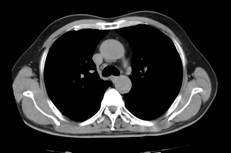

张××,男,56岁,外院CT增强示肝右叶“巨块型肝癌”,首次介入治疗后复查CT(2012年4月25日)所见瘤体大部栓塞,周围组织损伤小(图1a~b)。3年9个月后复查(2016年1月21日)见原瘤体明显缩小,上方肝实质复发病灶(图2a~b)。

图1a 图1b

图2a 图2b